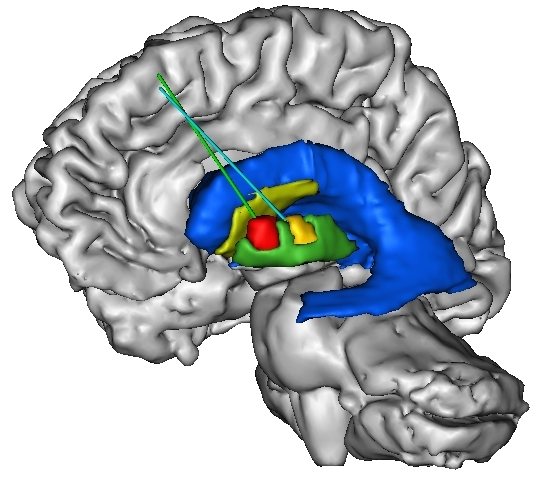

«Nuestro reto con la tecnología de ARN de interferencia es la manera de entregarla en el cerebro humano de manera sostenida, segura y efectiva», dijo Nolta, cuyo laboratorio ha recibido recientemente fondos del Instituto de Medicina Regenerativa de California para desarrollar un sistema de entrega de RNAi la enfermedad de Huntington. «Estamos explorando el uso de células madre humanas para crear fábricas de producción de RNAi en el cerebro.»

La Universidad de California en Davis equipo de investigación demostró por primera vez que las secuencias de ARN inhibitorias puede ser transferido directamente de las células del donante en las células diana para reducir en gran medida la síntesis de proteínas no deseadas del gen mutante. Para transferir el inhibidor secuencias de ARN en sus objetivos, el equipo de Nolta de la ingeniería genética las células madre mesenquimales (MSC), que se derivan de la médula ósea de donantes humanos no afectados. Durante las últimas dos décadas, Nolta y sus colegas han demostrado que las MSCs a ser seguro y eficaz de entregar vehículos de enzimas y proteínas a otras células. Ella dijo que encontrar que las MSCs también puede transferir directamente las moléculas de ARN a partir de una célula a otra, en cantidades suficientes para reducir los niveles de una proteína mutante en más del 50 por ciento en las células diana, es un descubrimiento que nunca se ha informado antes, y ofrece una gran promesa para un variedad de trastornos.